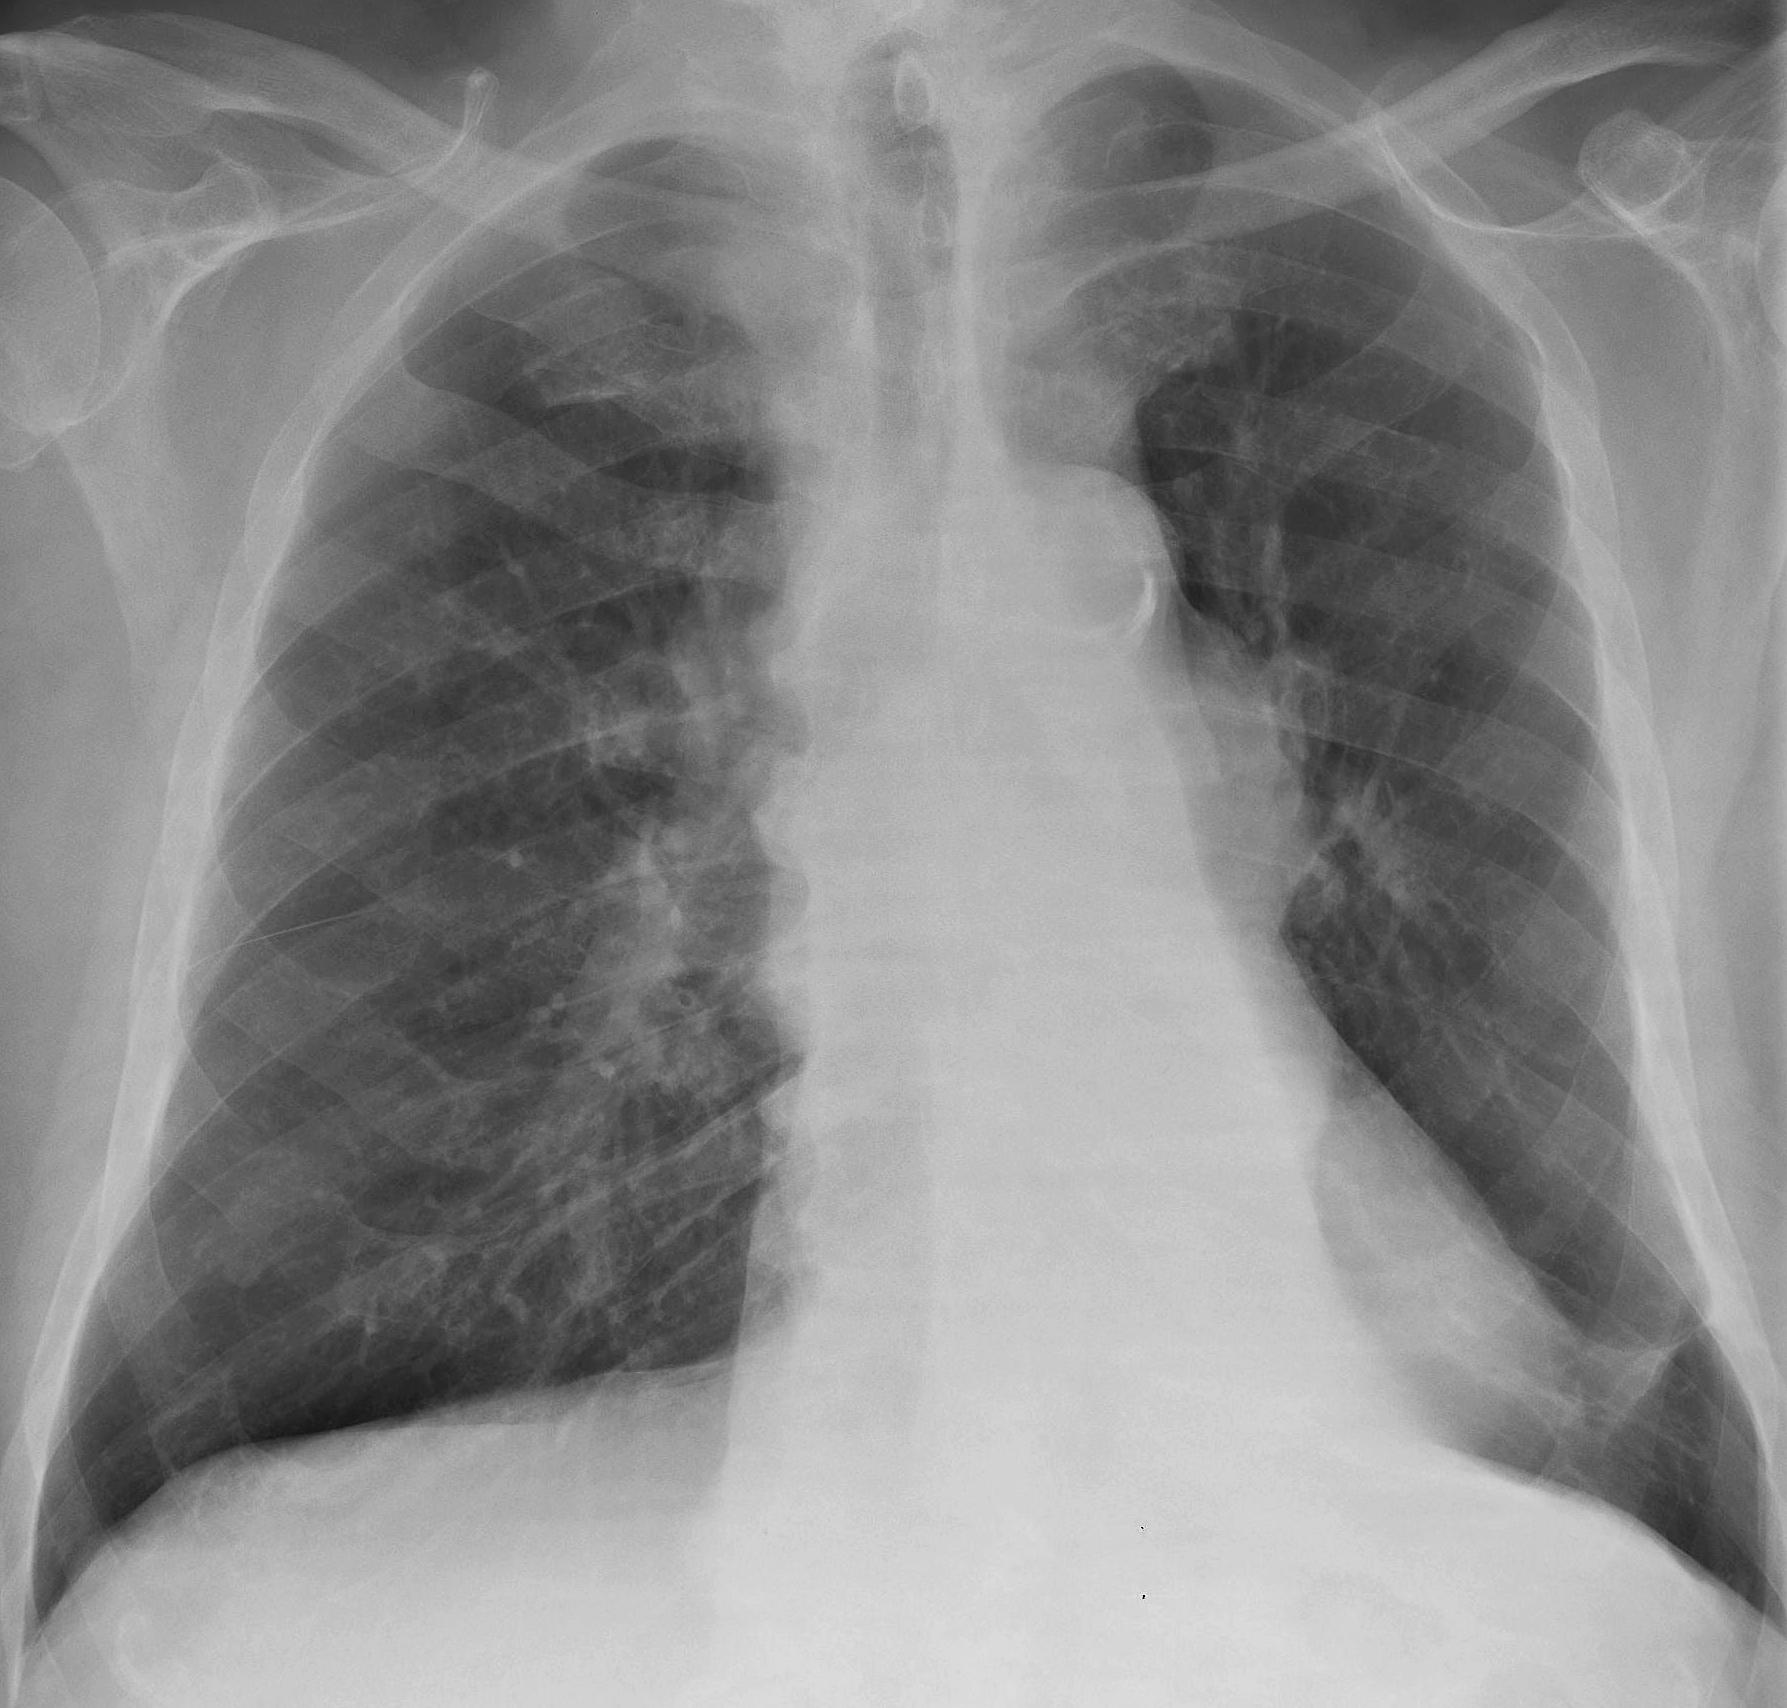

CA LLL collapse